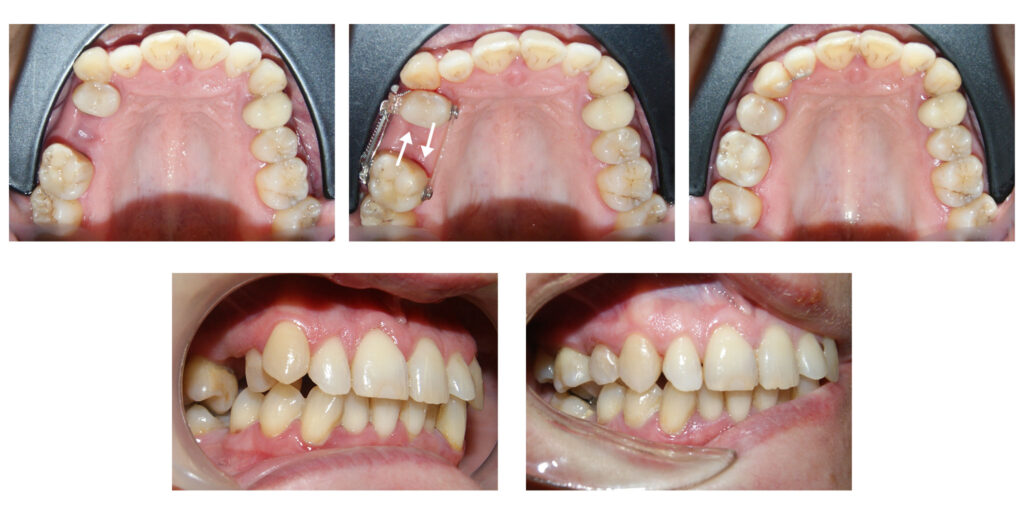

Redeschiderea spațiilor pentru caninii definitivi (a se observa că pe o parte spațiul era închis complet)